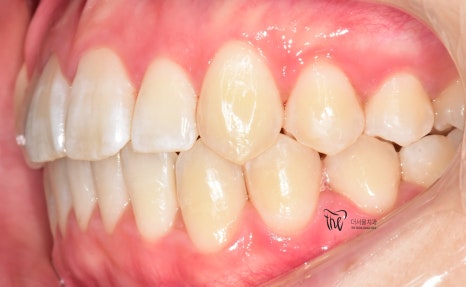

그러나, 좌측에서 바라봤을 때는 어금니들이

부정교합을 띄고 있는 것을 볼 수 있습니다.

즉, 거꾸로 물리는 반대교합의 양상을 보여주고

있고 이런 증세 때문에 턱관절의 통증까지도

같이 느끼고 있는 채로 내원을 하셨습니다.

즉, ‘턱관절 통증 치료 및 치열의 개선’

이 2가지를 함께 치료를 받고 싶어서 먼 길을

걸어서 오셨던 환자의 임상 증례입니다.